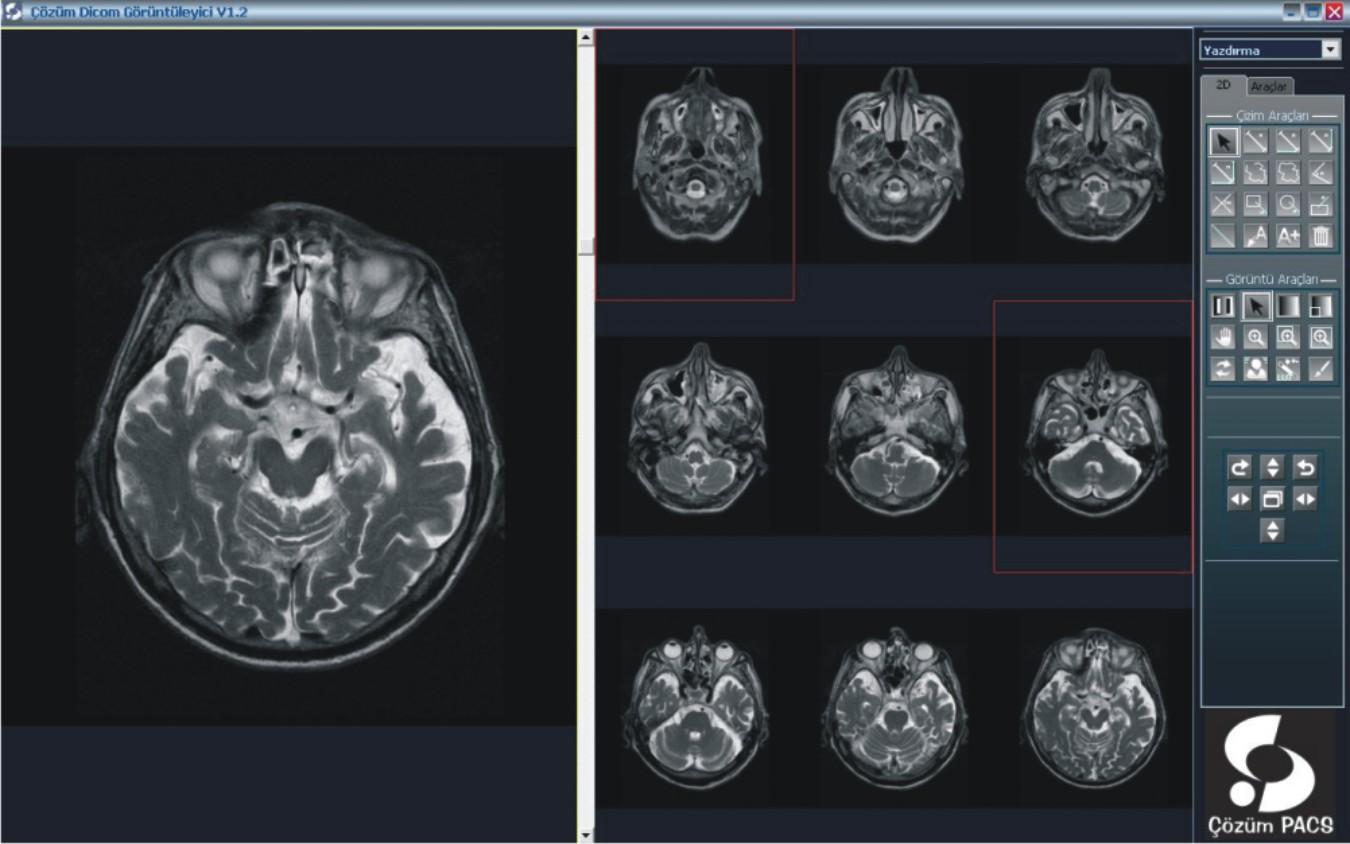

PACS (Picture Archiving And Communication System) alım işlemlerini sonuçlandıran hastane yönetimi “dijital hastane” olma yolunda emin adımlarla ilerliyor. Konu ile ilgili olarak, Başhekim Yardımcısı Dr. Muhammet Özgehan sistemin sağlayacağı avantajları üzerine Dergimize kısa açıklamalarda bulundu;

Hastanemizde bilgi yönetim sistemi olarak Çözüm HBYS'yi (Hastane Bilgi Yönetim Sistemi) kullanıyoruz. Güçlü bir entegrasyon sağlamak adına uluslararası standartlara haiz, tamamı Türk mühendislerine ait tek PACS olma özelliğindeki Çözüm PACS'ı tercih ettik.

PACS ile, dijital olarak elde edilen panoramik ve lokal radyolojik görüntüler (ultrasonografi, doppler, magnetik rezonans, tomografi v.b. cihazlardan elde edilen veriler) çevrimiçi ortamlarda dijital arşivleme yöntemleriyle saklanıyor. Kayıpsız bir şekilde, hızlı ve güven içinde saklanan bu görüntüler, gerektiğinde istemcide yeniden görüntülenerek kullanılabiliyor.

Merkezi veri tabanında bilgilerin depolanması ile oluşan dijital arşiv (görüntüler üzerinde işlem yapmaya izin verecek şekilde yüksek çözünürlükte saklandığı için ölçüm ve tanıya ilişkin işlemler kolaylıkla yapılabiliyor), bilgilerin yeniden kullanılmasını arşivlenen bilgilerin modern tanı yöntemleri ile incelenmesini sağlıyor. Dijital görüntüler üzerinde işlem ve ölçüm yapılabiliyor. Görüntüler ve raporların her an, her yerde (tüm iş istasyonları üzerinden sorgulama yapılarak) ulaşılabilir olmasına ve görüntü işleme ve ölçüm (mesafe, açı, uzunluk, yoğunluk) yapılabilmesine imkan sağlıyor.

PACS, tanı ve teşhislerde daha doğru sonuçlar elde edilmesini sağlayarak  sonuçları  yorumlama ve raporlama süresini hızlandırıyor. Görüntülerin karşılaştırılması ve radyolojik bulguların geriye dönük değerlendirilmesi, karşılaştırmalı raporların incelenmesi, hekimin hastalığın gelişim sürecini daha iyi kavramasını ve doğru teşhisi daha hızlı bir şekilde koyabilmesini sağlıyor. Yedeklenen PACS görüntüleri istenildiğinde hastalara CD-DVD halinde veriliyor.